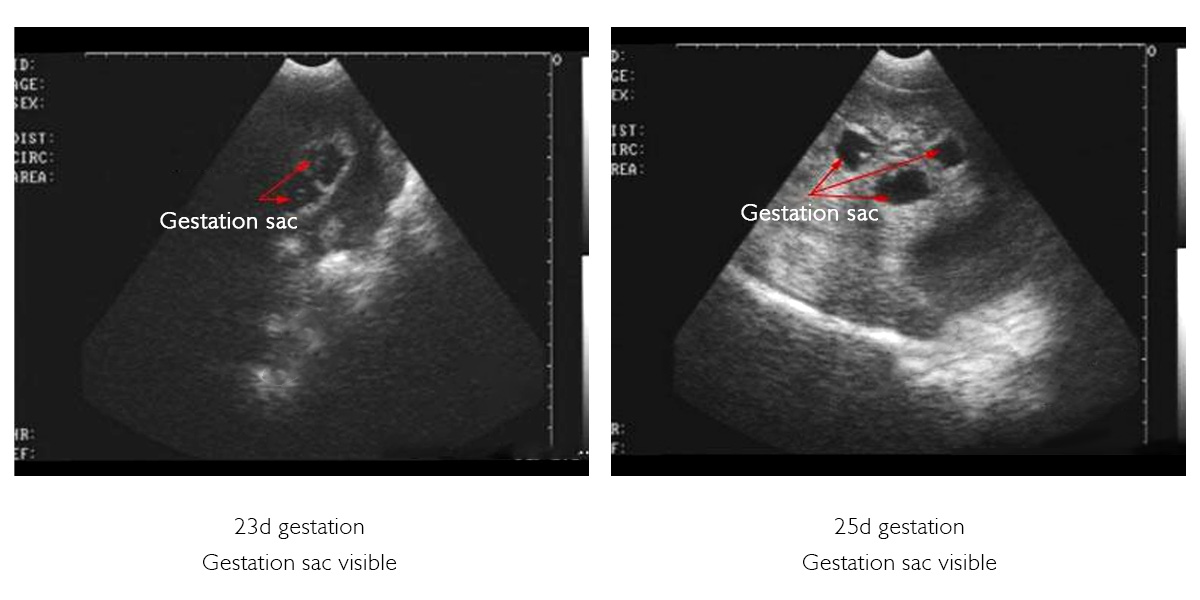

Traditional manual palpation requires more than 30 days after mating to confirm pregnancy, which not only has high error rates but also carries the risk of mechanical miscarriage. With the help of veterinary ultrasound, pregnancy can be accurately confirmed as early as 25 days after mating, with the amniotic sac and foetal heartbeat clearly identifiable with over 98% accuracy. The optimal time for a pregnancy test is between 25 and 30 days after mating, when the amniotic sac is most clearly visible as a regular, circular dark cavity, making it easier to identify. If the sac develops beyond this period, its shape becomes irregular, making detection less straightforward than in the early stages. Nevertheless, it remains easily distinguishable from the empty uterine cavity when compared to imaging.